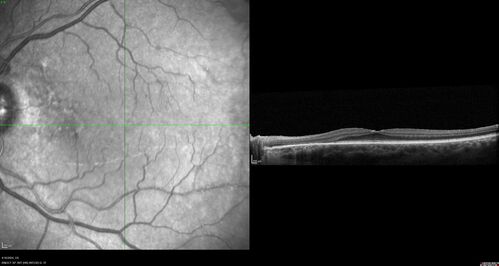

Posterior Pigment Dispersion Syndrome

81 year old man with cataract surgery 30 years ago and normal vision who had bilateral vitrectomy for dense floaters and has pigment on his IOL surface and all over the retina (but not on the cornea) VA 20/25 OU